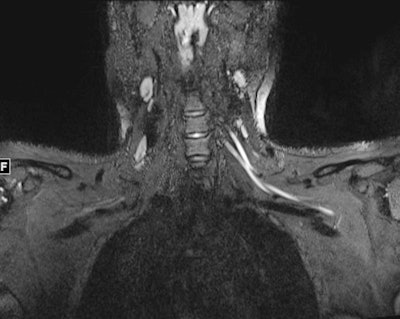

An MR image of a patient in their early 20s shows nerve injury of the left brachial plexus in the neck. The patient experienced left arm weakness and pain after recovering from COVID-19 respiratory illness, which prompted them to see their primary care physician. As a result of the MRI findings, the patient was referred to the COVID-19 neurology clinic for treatment. Image and caption courtesy of Northwestern University.Determining the cause makes treatment more effective, according to the team. If the cause is due to injury from prone positioning, a patient would be referred for rehabilitation or peripheral nerve surgery. If nerve damage has been caused by inflammatory response, the patient should see a neurologist. And if the damage is caused by hematoma, blood thinner medications should be adjusted and surgery may be necessary, according to the group.

Ultrahigh-resolution ultrasound and MR neurography (which visualizes the peripheral nerves) can localize the problem and assess the severity of nerve damage and whether that damage has affected the muscles, according to the team.